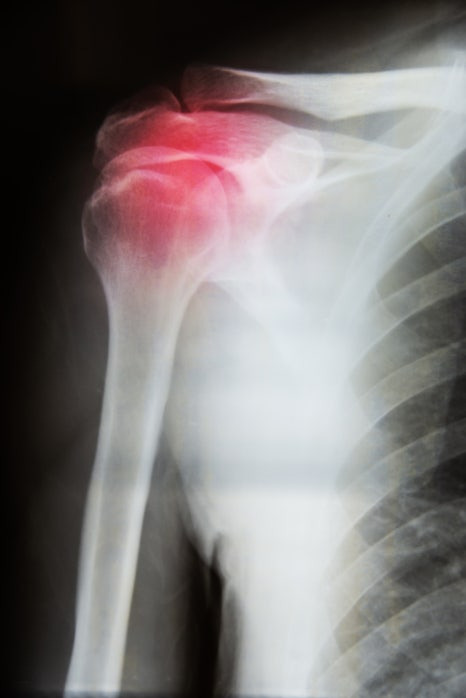

석회성건염이란? - 어깨 힘줄에 쌓이는 석회

석회성건염은 어깨 관절을 움직이는 힘줄 특히 회전근개 힘줄 내부에 칼슘 성분이 침착되면서 염증 반응과 통증을 동반하는 상태를 말합니다. 겉으로 보기에는 뼈나 관절에 큰 이상이 없어 보여도 힘줄 안쪽에서 변화가 생기면서 불편감이 시작되는 것이 특징입니다.

석회성건염은 통증이 서서히 심해지기보다 갑자기 강해졌다가 어느 순간 완화되는 흐름을 보이는 경우가 많아 일시적인 증상으로 오해되기 쉽습니다. 그러나 이런 증상이 반복될수록 어깨 힘줄과 관절에는 부담이 계속 누적되고 일상 동작에서 불편감이 점점 커질 수 있습니다.

특히 팔을 들어 올릴 때 어느 각도에서만 유독 통증이 심해지거나 가만히 있어도 어깨 깊숙한 곳이 욱신거리는 느낌이 지속된다면 석회성건염일 가능성이 높습니다.